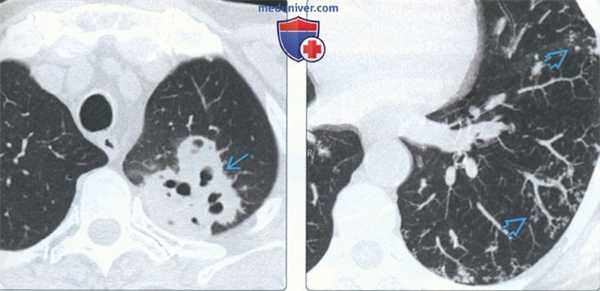

(Слева) На аксиальной КТ без КУ у пациента 62 лет с иммунодефицитом и пневмонией, вызванной Nocardia, в верхней доле левого легкого визуализируется опухолеподобный участок консолидации с множественными фокусами кавитации. Диагноз пневмонии, вызванной Nocardia, был выставлен на основании бронхоальвеолярного лаважа.

(Справа) На аксиальной КТ без КУ (MIP) у пациента с инфекционным целлюлярным бронхиолитом бактериальной этиологии в нижней доле левого легкого визуализируются мелкие сгруппированные очаги в виде «дерева в почках».

• Кавитация и пневматоцеле (золотистый стафилококк), абсцесс и гангрена легкого (Klebsiella pneumoniae)

• Разветвленные структуры и очаги в виде «дерева в почках»:

о Микобактериальные, бактериальные, вирусные инфекции